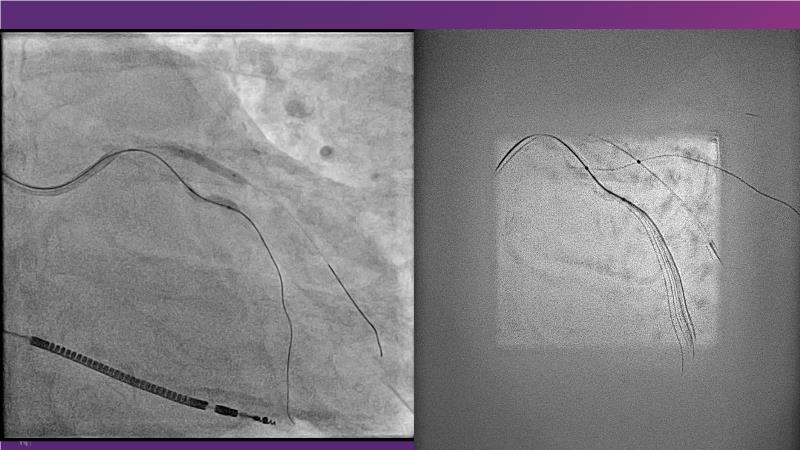

With this session, keep up to date on the evidence, trials and outcome data for intravascular lithotripsy in severely calcified lesions. Learn how to use this technique in real-world patients and understand its role in the treatment algorithm for severely calcified coronary lesions.

- To learn how to use intravascular lithotripsy in real-world patients with severely calcified coronary lesions